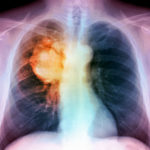

La configurazione dei “fattori di virulenza” consente alla tubercolosi di invadere i polmoni

L’agente patogeno batterico che causa la tubercolosi è un maestro dell’inganno, un re dei trucchi intelligenti: un agente nemico che non solo si infiltra, ma può diventare un clandestino a lungo termine nei polmoni dei pazienti.

Il Mycobacterium tuberculosis non solo elude la sorveglianza del sistema immunitario, ma invade audacemente i macrofagi polmonari, le stesse cellule che dovrebbero distruggerlo. Peggio ancora, i batteri non solo invadono: possono nascondersi indefinitamente nei macrofagi, normalmente i bruti del sistema immunitario, in grado di inghiottire e trasformare gli infiltrati in detriti innocui. M. tuberculosis trasforma la sceneggiatura in una storia completamente diversa.

Ora, gli scienziati in Francia hanno svelato per la prima volta il devastante primo passo nel processo di infezione, che è guidato da potenti fattori di virulenza noti come dimiocerato di feniocerolo o più semplicemente come DIM. Questi lipidi complessi promuovono l’ingresso di M. tuberculosis nei macrofagi polmonari.

La tubercolosi (TB) si diffonde nell’aria attraverso la tosse, lo starnuto, la saliva e persino conversazioni casuali a distanza ravvicinata. L’infezione è causata da un microbo resistente che può sopravvivere fino a sei mesi sulle superfici, a condizione che il sito sia privo di esposizione solare o luce ultravioletta prodotta artificialmente.